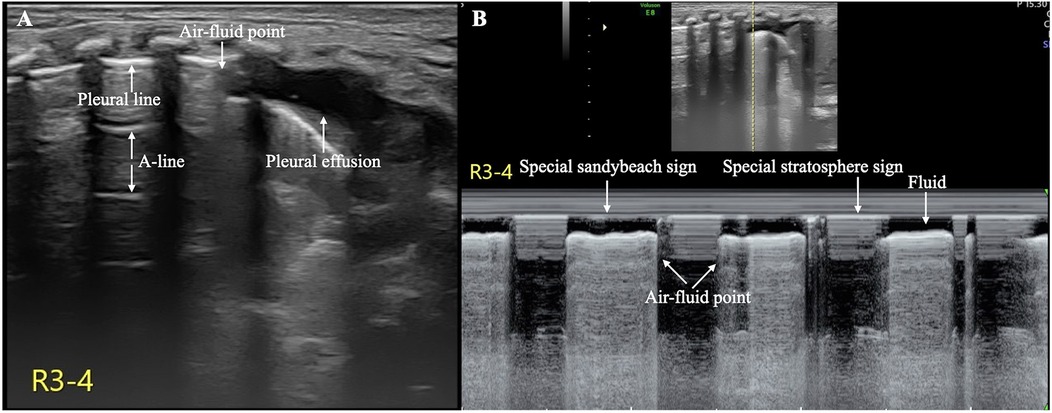

The patient's condition was relatively stable on the first and second days after birth, with noninvasive respiratory support maintaining stable vital signs. However, her respiratory distress suddenly worsened on the third day after birth, and the oxygen concentration required invasive respiratory support to maintain normal blood oxygen saturation without any obvious triggers. LUS reexamination revealed clear pleural lines and A-lines on B-mode ultrasound of the left anterior chest, axilla, and back. The stratosphere sign appeared on M-mode ultrasound. Real-time ultrasound revealed the disappearance of lung sliding. According to the diagnostic and grading criteria of PTX, this child meets the diagnostic criteria for severe PTX in the left thoracic cavity (9–11) (Figure 2, Supplementary Video S1). Moreover, ultrasound signs indicating a moderate degree of PTX were also observed in the anterior chest and the upper axillary region of her right thoracic cavity (9–11). In the lower field of the right axilla, an anechoic dark area was observed, and alternating visibility of the lung sliding was observed between the upper and lower fields on real-time ultrasound. Under M-mode ultrasound, these areas presented as alternating characteristics between the beach sign and the stratosphere sign, similar to the lung point (11, 12), confirming a small amount of pleural effusion combined with moderate pneumothorax, specifically hydropneumothorax (Figure 3, Supplementary Video S2).

Figure 3. Hydropneumothorax in the right thoracic cavity. The pleural line and A-line are clearly displayed in the upper lung field, and an anechoic dark area is observed in the lower lung field on B-mode ultrasound (A) On real-time ultrasound, a demarcation point between the gas and fluid interfaces is observed; this kind of demarcation point is referred to as the air–fluid point in this paper (Supplementary Video S2). M-mode ultrasound revealed the air–fluid points as alternating points of the characteristic sand on the beach sign and the characteristic stratosphere sign (B) These findings confirmed that both pleural effusion and pneumothorax coexisted (i.e., hydropneumothorax).

Ultrasound is a simple and effective imaging procedure for the diagnosis of pleural effusion and pneumothorax (8–11). However, when both conditions occur simultaneously, ultrasound techniques for diagnosing these conditions and identifying specific ultrasound imaging features observed in the field of neonatology have not yet been explored. The infant in our case study showed signs of PTX, such as clear pleural lines and A-lines, as well as pleural effusion indicated by the absence of echoic dark areas, simultaneously on B-mode ultrasound. On real-time ultrasound, gas and fluid alternate at their interface, and this type of air–fluid demarcation point is referred to as the “air–fluid point” in this paper. Under M-mode ultrasound, gas signs (a characteristic stratospheric sign) and liquid signs (a characteristic sand on the beach sign) alternately emerge, and the point where they alternate is called the “air‒fluid point”. Therefore, although hydropneumothorax is extremely rare in clinical practice, accurate diagnosis via ultrasound is feasible provided that technicians are highly skilled in ultrasound diagnostic techniques for pneumothorax and effusion. Notably, the “normal” findings on B-mode ultrasound for an infant with breathing difficulties do not necessarily indicate true normality; it is necessary to observe pneumothorax under real-time ultrasound and, if necessary, to conduct M-mode ultrasound for verification.